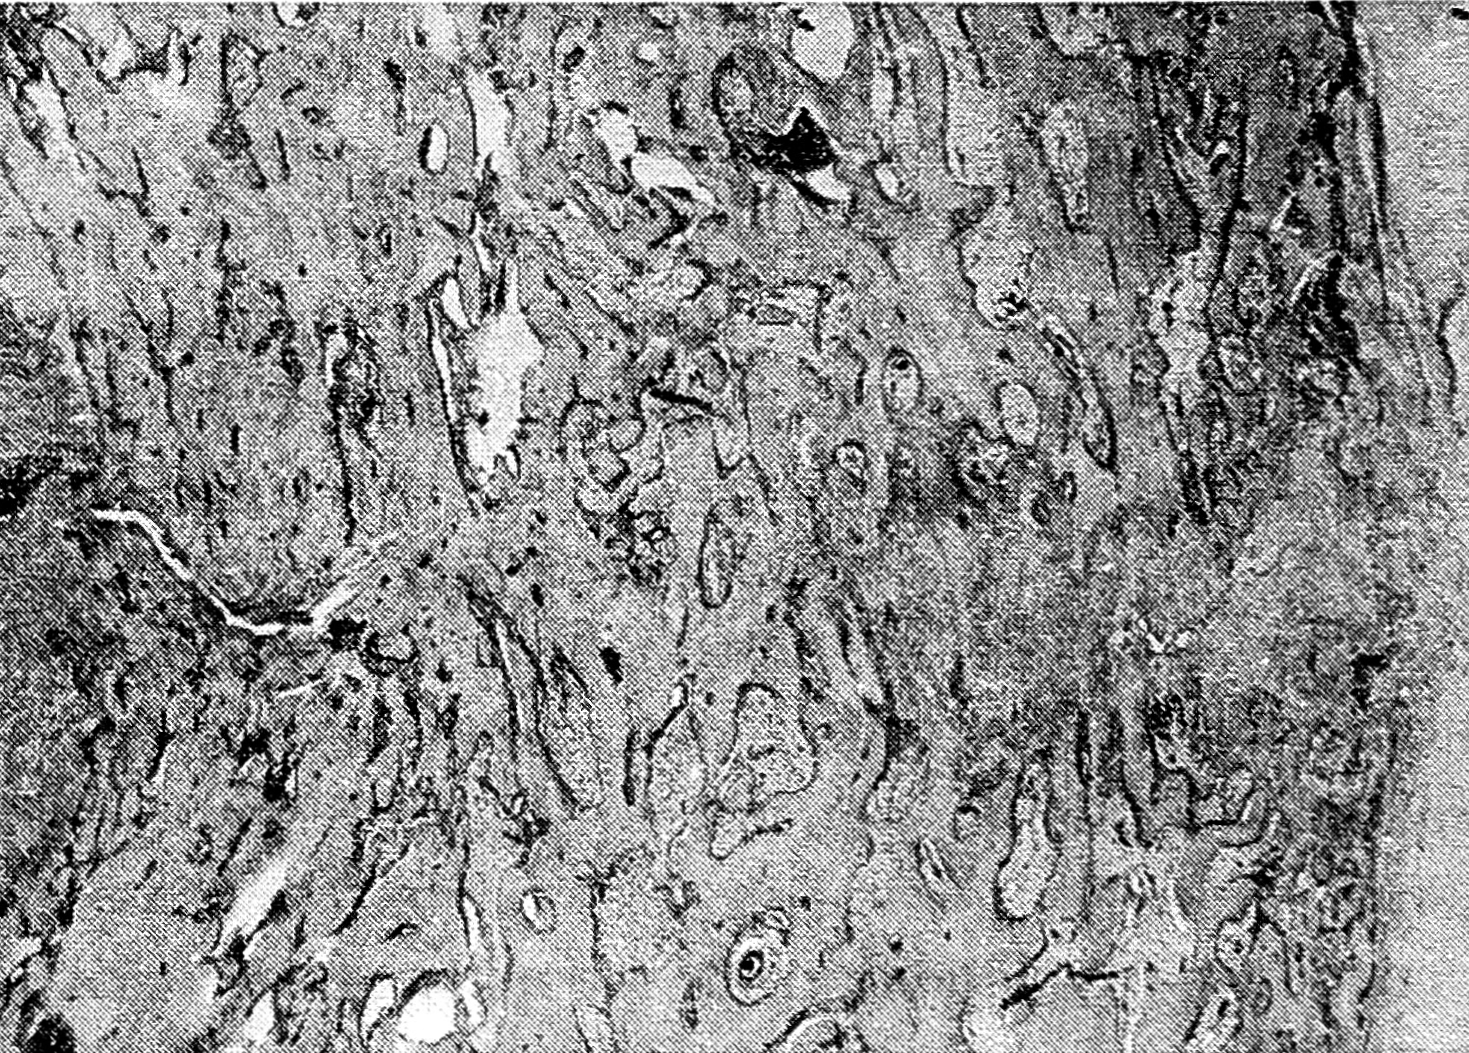

Результаты и обсуждение. Изучение динамики рентгенологических и морфологических показателей (форма и структура костей) в эксперименте показало, что функциональное перенапряжение неповрежденной кости уже ко 2—3-м суткам активизирует периостальное и эндостальное костеобразование, однотипное репаративной реакции при переломах. Этот процесс костеобразования, протекающий на фоне острого расстройства внутрикостного кровоснабжения и называемый репаративной реакцией на перенапряжение (рис. 1), приводит к локальному утолщению кости — гиперостозу.

Рис. 1. Репаративная реакция на перенапряжение (16-е сутки функциональной перегрузки).

Окраска гематоксилином и эозином. Ув. 12.